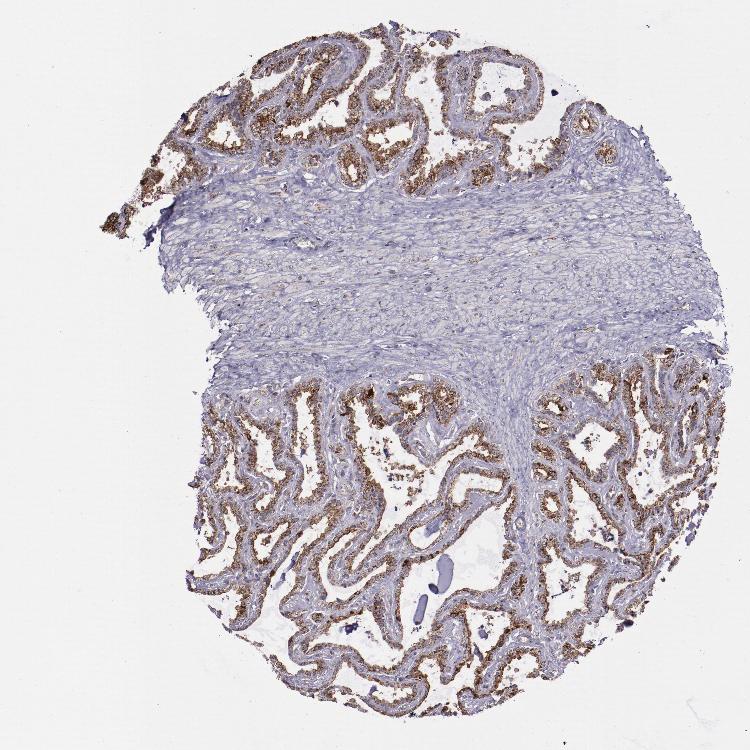

SEMINAL VESICLE - Antibody stainingi

Antibody staining in the annotated cell types in the current human tissue is reported as not detected, low, medium, or high, based on conventional immunohistochemistry profiling in selected tissues. This score is based on the combination of the staining intensity and fraction of stained cells.

Each image is clickable and will lead to virtual microscopy that enables deeper exploration of all samples and also displays staining intensity scores, fraction scores and subcellular localization as well as patient and tissue information for each sample.

Antibody HPA002192

Glandular cells High